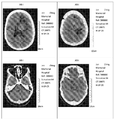

- 238000002591 computed tomography Methods 0.000 description 6

- 210000004556 brain Anatomy 0.000 description 4

- 210000001652 frontal lobe Anatomy 0.000 description 3

- 210000001152 parietal lobe Anatomy 0.000 description 1